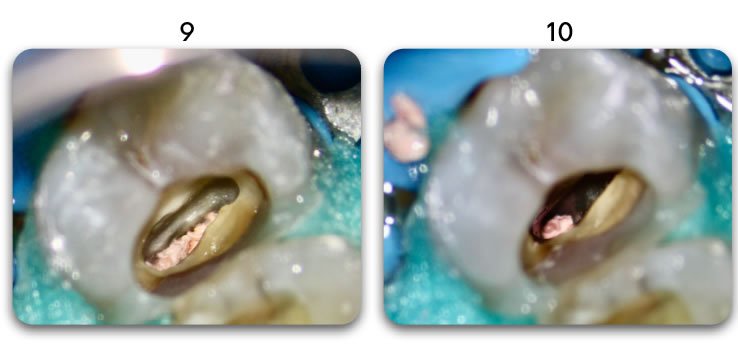

Retain 100% of remaining healthy tooth structure

- Biolight® DRILL-FREE adapts to all shaped canals, while conserving all remaining healthy tooth structure.

- There is no need to drill out portions of canals to accommodate post spaces.

- Easily place multi-posts in multiple canals as the post bends with the natural canal shape.

YES. Biolight® DRILL-FREE provides a solid, anatomical anchoring to remaining tooth structure. By arranging reinforcement towards the periphery of the canal walls, support of the core is improved. The concept is similar to how reinforcement steel rods and used in concrete structures, where many smaller rods are placed around the perimeter of the concrete. In addition, all risks associated with drilling are eliminated.